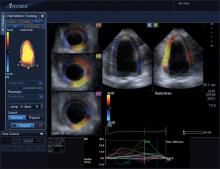

Cardio-oncology is an emerging field that combines the expertise of both cardiology and oncology to assess and treat cancer patients for the second leading cause of death among cancer survivors — cardiovascular disease brought on by their treatments. Specific types of chemotherapy and chest directed radiation therapy are known to cause cardiac dysfunction, mainly due to cardiotoxicity — the symptoms of which may not present until months or even years after cancer treatment.